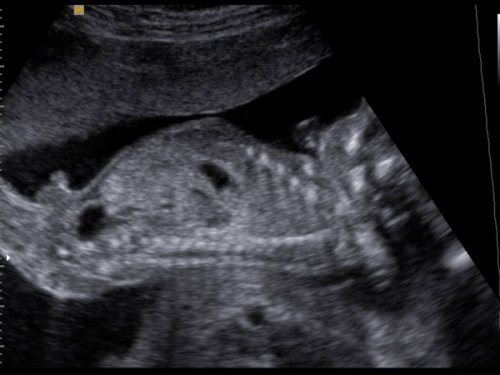

mi is megjöttünk, minden ok. nagyon szégyenlős volt, szinte semmit nem mutatott az arcából. a placentát, mint egy kismama a szopipárnát ölelte, és jól odabújt. amúgy egészséges, pöckét mutogatta, így nekünk is tuti a fiú. auszrtál volt az uhás nő, jófej volt, alapos.

Nálam csak 1 profi vizsgálódott, ő magyarázott a többieknek. Minden rendben volt, egészséges, méreteket nem mért, de mingnéztünk minden artériát, vénát, belső szervet, agykamrákat, és még egy csomó latin nevű dolgot. Nade a lényeg (amellett, hogy egészséges) KISFIÚ (tovább kékül a tábli :D :D :D )

CD-t én is kaptam, képeket minnyá nézek róla. Ja, a képek nálam se lettek nagyon jók, mert ő is belefúrta magát a lepénybe. Ettől függetlenül szépen látszott, ahogy integet, kalimpál, fogja a fejét stb.

Jó volt, sokáig nézték a babócát, egy nagyon profi géppel, ahol mindenféle áramlást is vizsgáltak (pl.: főerek, köldökzsinórban lévő áramlást-itt még hang is volt, nagyon érdekes volt). Megnézték még egyszer a nemét is, és 100%, hogy kisfiú! Sokat mosolygót a baby, de végére elfáradt, és bújt el a kezei mögé, nagyon cuki volt!